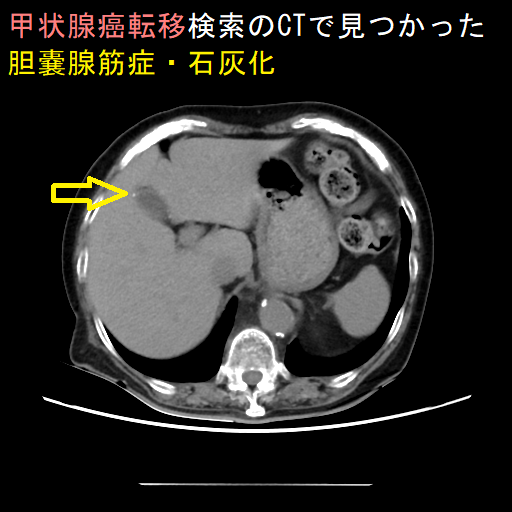

胆嚢腺筋症(adenomyomatosis of gallbladder)とは、胆嚢粘膜が筋層内で増殖して、胆嚢壁の肥厚を来す病態。ほとんどのケースで無症状だが、胆石を合併したり胆嚢炎を引き起こすることがあります。甲状腺と胆嚢腺筋症の間に、直接的な関係はありません。